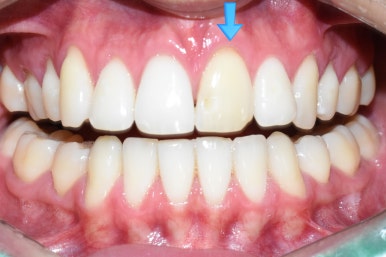

이 외국 환자분은 오래 전에 치아 하나가 변색되기 시작했고

그래서 2년 전 쯤에 본인 나라(유럽)에서 신경치료를 시도 했으나 신경관이 너무 좁아서 신경관을 찾지 못해

중단된 상태였습니다.

위 앞니 하나가 아주 변색이 된 상태 (치료 전)

변색된 앞니

딱 눈에 보이는 가장 큰 앞니 하나가 변색이 너무 심하니

환자분이 스트레스 받을 만 했고,